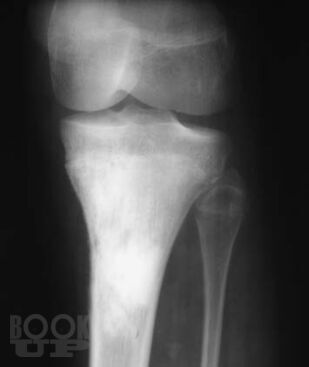

Рентгенологические и ультразвуковые исследования при заболеваниях суставов

Семизоров А. Н. Рентгенологические и ультразвуковые исследования при заболеваниях суставов : Пособие для врачей / А. Н. Семизоров, С. В. Романов. - М. : Видар-М, 2008. - 216 c. - ISBN 9785884291140. - Текст : электронный // ЭБС "Букап" : [сайт]. - URL : https://www.books-up.ru/ru/book/rentgenologicheskie-i-ultrazvukovye-issledovaniya-pri-zabolevaniyah-sustavov-9194384/ (дата обращения: 23.05.2026). - Режим доступа : по подписке.

Предлагаемая книга является дальнейшим развитием вышедшего ранее пособия «Ретнгенологическое и ультразвуковое исследование при заболеваниях

суставов».

Иллюстративная часть материала дополнена рентгенограммами, расширен

и углублен текст. В книге изложены основы рентгенологической и ультразвуко

вой диагностики дегенеративнодистрофических, воспалительных и других

заболеваний суставов. Представлены особенности диагностики при наиболее

часто встречающихся в клинической практике заболеваниях суставов.

Пособие рассчитано на рентгенологов, врачей УЗИ, ортопедов и врачей других специальностей.